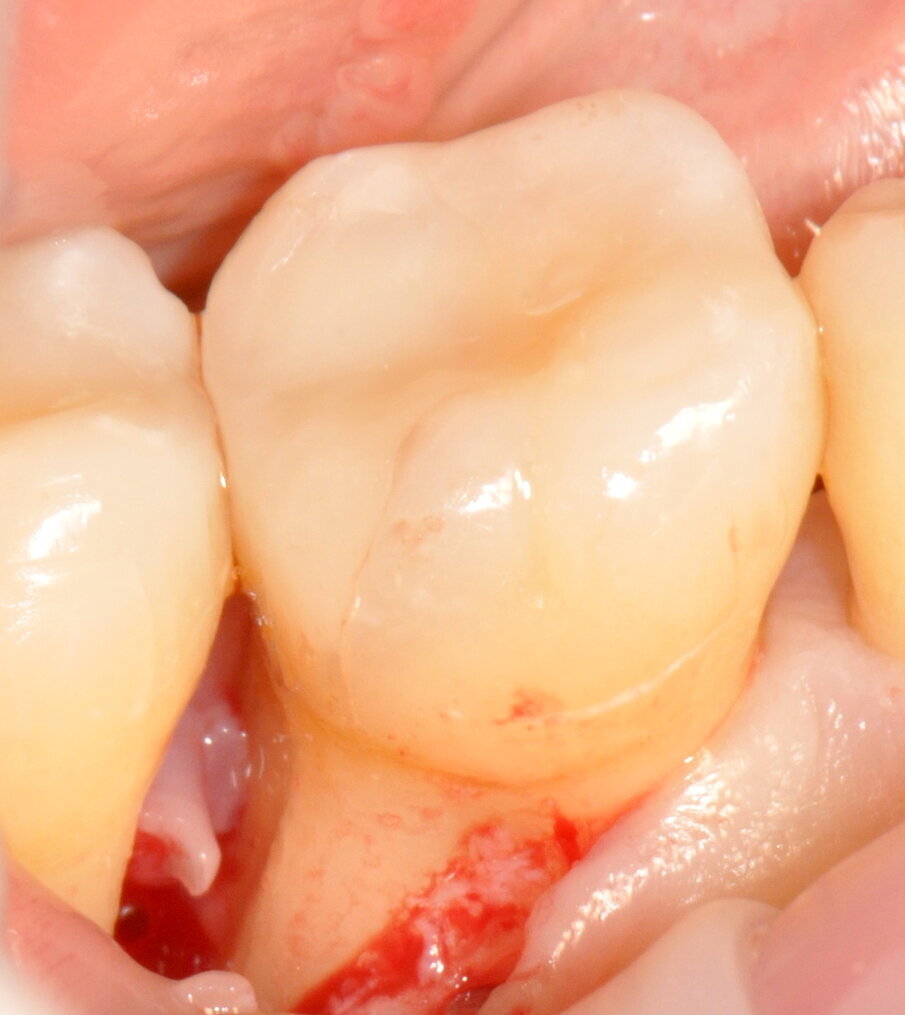

Tuttavia, nei siti DV e MV degli elementi 4.6. e 4.7 si riscontra nuovamente BOP e SOP positivo. Si decide dunque di effettuare un intervento di chirurgia ricostruttiva, finalizzato alla chiusura del difetto intra-osseo e programmato ad una settimana dalla seduta di richiamo di igiene orale professionale (GBT®). Dopo uno sciacquo per 60 secondi con collutorio a base di Clorexidina 0.12% e Cloruro di Cetilpiridinio (Paroex® GUM®), si esegue anestesia locale plessica con Articaina 4% con adrenalina 1:100.000 e disegno di un lembo M-MIST (Modified-Micro Invasive Surgical Technique)5. La scelta di questo tipo di lembo è volta alla massima preservazione della vascolarizzazione del sito chirurgico e al mantenimento della papilla interdentale.

Fig. 7 - Disegno del lembo con preservazione della papilla interdentale.

Fig. 8 - Scollamento del lembo a tutto spessore.

Fig. 9 - Difetto esposto completamente.